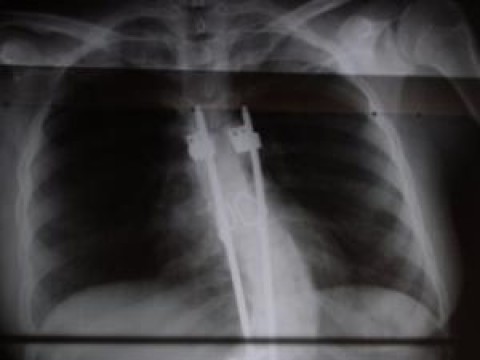

Τέλος στη ταλαιπωρία χιλιάδων παιδιών βάζει μια μαγνητική ράβδος που τοποθετείται στην σπονδυλική στήλη, μεγαλώνει μαζί με τα οστά και θεραπεύει την σκολίωση!

Το εντυπωσιακό είναι ότι μία μικρή τομή δύο εκατοστών, φθάνει για να εμφυτευθούν μία ή δύο ράβδοι κατά μήκος της σπονδυλικής στήλης, πάνω στην οποία βιδώνονται. Η ράβδος εμπεριέχει έναν μαγνήτη ώστε να μπορεί ο γιατρός να προσαρμόζει το μήκος της με το εξωτερικό τηλεχειριστήριο.

Διαθέτει επίσης έναν αισθητήρα πίεσης, που ειδοποιεί το τηλεχειριστήριο όταν έχει φτάσει στο ιδανικό μήκος.

Η εγχείρηση διαρκεί τρεις ώρες και το παιδί μένει στο νοσοκομείο για μία εβδομάδα.